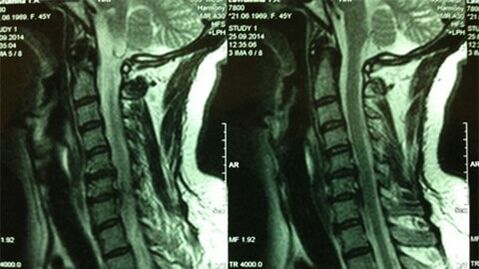

- X-ray of the cervical service;At the initial stage of the process, the MRI of the cervical service will be more informative - it will guarantee a high quality visualization of the solid and soft tissues - will show the condition of the intervertebral discs, the presence of osteophytes, deformations, damage to the nerve roots and the blood vessels;will assess the state of ligaments, muscles, bone tissue;